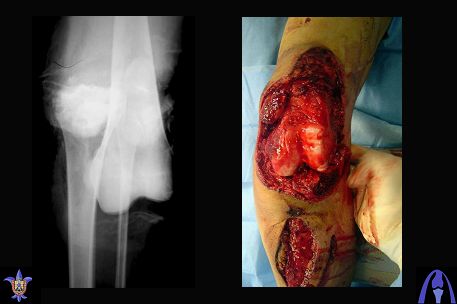

Re: open dislocation of the knee joint

послал Djoldas Kuldjanov 01 Ноябрь 2007, 09:02

Снимки прошлых публикации из моего Power point